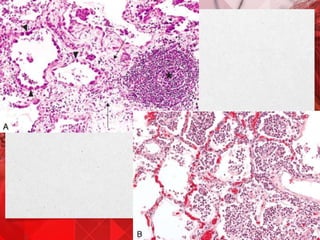

Aumento de 4X

GRANULOMA PULMÃO - ESQUISTOSSOMOSE

Aumento de 20X

Aumento de 60X

CÉLULAS GIGANTES

Aumento de 4X GRANULOMAPULMÃO - ESQUISTOSSOMOSE